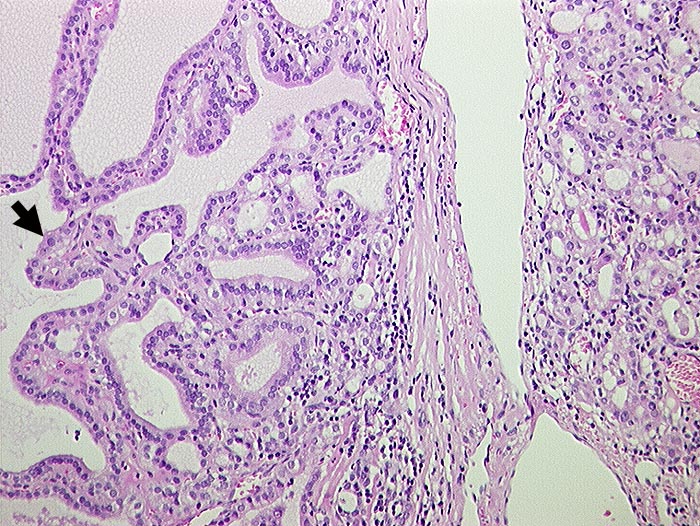

Morbus Basedow: Makropapillen

Links im Bild makropapilläre Proliferationen und Sanderson-Polster. Rechts aktivierte Follikel mit grossen Epithelzellen und praktisch fehlendem Kolloid.

Makroskopisch diffus vergrösserte Schilddrüse mit auffallend hellem homogenem mittellobuliertem Parenchym.